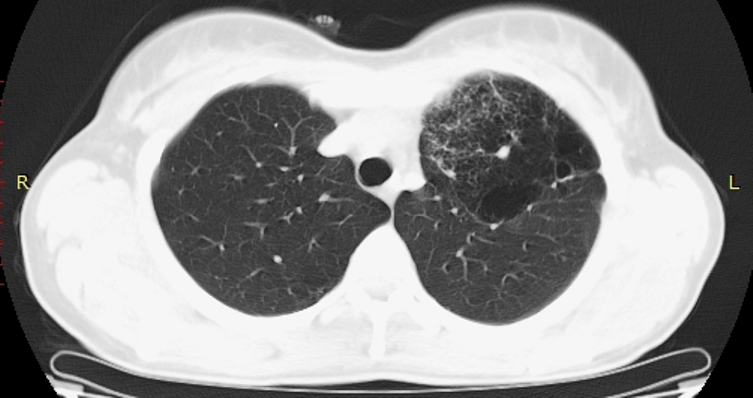

Женщина 35 лет. Жалоб нет. Профилактическая ФГ - дополнительная тень у головки левого корня (снимок пленочный, маленький...не переснимал, так как вряд ли удасться добиться хорошего качества). Подняты пленочные ФГ за 2009 и 2010 гг - есть небольшая деформация легочного рисунка и просветления без четкой контурации у левого корня (естественно - все это ретроспективно, с учетом уже известной информации).

Это НЕ "сотовое легкое"

Отправлять на нормальную КТ с контрастом. Думаю, будет аномалия сосудов, дисгенезия легкого слева. Представленных картинок явно недостаточно, нужны сканы в средостенном окне с контрастом.

Можно подумать  об артерио-венозной мальформации.Тем более имеются характерные изменения в окружающей лёгочной ткани и прилежащих бронхах. Конечно, нужно контрастировать.

Явно аномалия, нет сомнений. Но секвестрация сомнительна, хотя....

Пока, без Дайкома, можно предположить БЭЛ (локальную).

БЭЛ: Буллезная эмфизема легких. Причины: от воспалительных процессов до врожденных ферментативных нарушений.

имхо:скорее всего гипогенезия верхней доли левого лёгкого  с  буллезно-фиброзными проявлениями.